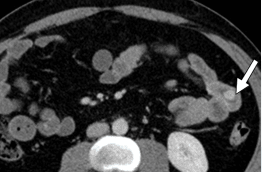

В 50-90% случаев на поверхности злокачественных клеток нейроэндокринных опухолей (НЭО) наблюдается увеличение количества соматостатиновых трансмембранных рецепторов (somatostatin seven-transmembrane-domain receptor, SSTR). На этом основано применение радионуклидных методов диагностики. При выполнении позитронно-эмиссионной томографии (ПЭТ\КТ) для диагностики НЭО предназначены радиофармпрепараты 68Ga-DOTA-TATE (DOTA-TATE, меченый галлием-68) и 68Ga-DOTA-NOC (DOTA-NOC, меченый галлием-68), как обладающие сродством к большинству подтипов SSTR .

Нередко возникают ситуации, когда чувствительность ПЭТ/КТ с 68Ga-DOTA-TATE и 68Ga-DOTA-NOC снижена. В таких случаях возникает необходимость выполнения исследования с другим радиофармпрепаратом – 18F-фтордезоксиглюкозой (18F-ФДГ).

Рисунок 4. Накопление радиофармпрепарата 68Ga-DOTA-TATE пораженными лимфатическими узлами у пациента с НЭО прямой кишки.